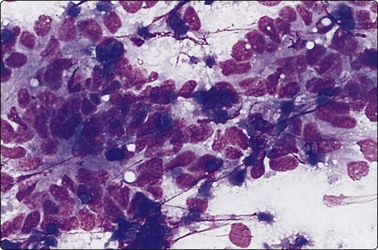

image image

Fig. 6.26 Hurthle cell carcinoma

(A) Similar pattern as Figure 6.25B of trabecular groups of oxyphil cells (MGG, HP); (B) Large polygonal cells with well-defined cell margins, basophilic cytoplasm, vesicular nuclei and macronucleoli (MGG, HP).

HCTs, constituting 1.5–10% of thyroid tumors, represent a controversial pathological entity,142 regarding both their behavior and classification (whether they represent metaplasia in follicular or papillary neoplasms or constitute a distinct entity). Most tumors are encapsulated, and capsular and/or vascular permeation are standard criteria of malignancy. Recent reports suggest that Hurthle cell carcinoma may be a more aggressive tumor, distinct from FC.143 Rare familial cases of aggressive, metastasising Hurthle cell carcinoma have been reported.144

Smears from HCT yield abundant material consisting of large, polygonal Hurthle cells with oval nuclei and abundant, well-defined, granular cytoplasm. Tumor cells appear singly, in acinar arrangement, and in monolayered sheets of variable sizes.145,146 Nuclei are eccentrically placed. Occasional cells may be ovoid or rounded. Nuclear pleomorphism may be present but is not as common in adenomas as in non-neoplastic lesions like HT. Occasional small syncytial tumor cell clusters and naked nuclei may be seen. Carcinomas show relatively smaller Hurthle cells with monomorphic or pleomorphic nuclei, macronucleoli and ill-defined cytoplasm. Crowded sheets, syncytial tumor cell clusters of variable sizes and naked nuclei may be present.90 Computerized interactive morphometric analysis of nucleolar features may be helpful in distinguishing benign from malignant lesions.147 However, due to frequent morphological overlap, a cytological diagnosis of HCT is preferred, with further categorization deferred for histological study. Galectin 3 immunostain has been shown to stain Hurthle cell adenomas.55 Combination of galectin 3 and HBME has been demonstrated to show 99% sensitivity and 88% specificity in tumors composed of Hurthle cells (Hurthle cell adenomas, carcinomas and oncocytic variant of PC).148